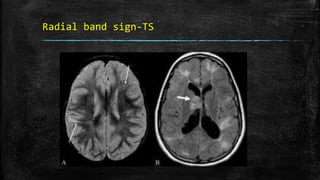

Radial band sign-TS

• #102 Radial band sign. Proton density-weighted axial image of the brain (A) in a patient with tuberous sclerosis shows hyperintense bands in the white matter radiating from the ventricular margin to the subcortical region (arrows). FLAIR axial MRI image (B) shows irregular hyperintense areas in the subcortical white matter suggestive of subcortical tubers. A large hyperintense nodule is seen in the region of the foramen of Monroe, representing a subependymal giant cell astrocytoma (thick arrow)